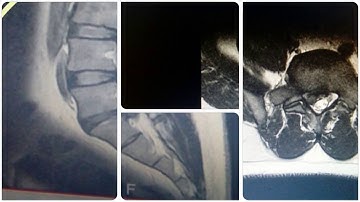

"Principles of Transforaminal Approach - Biportal Endoscopic Spine Surgery: Part 1" - Dr. D.J. Choi